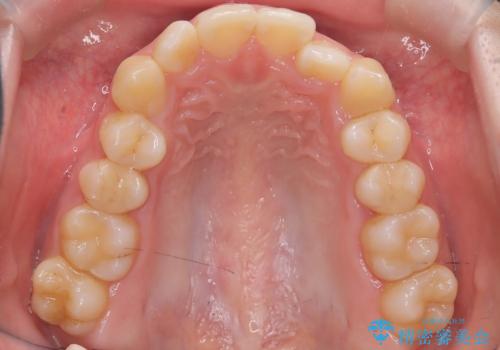

- 右上の前歯(2番)が下の歯より内側に入っている反対咬合を主訴にご来院されました。精密な検査の結果、この反対咬合を解消するためには、右上の歯列に前歯を出すためのスペースを確保する必要があると判明しました。患者様のご希望に合わせ、透明で目立たないインビザライン(マウスピース矯正)による治療計画を立案。奥歯全体を奥へ動かす遠心移動でスペースを作り、反対咬合を解消することを目指します。

今回の矯正治療では、透明なマウスピース型の装置インビザラインを使用しました。治療は、緻密なデジタル計画に基づき、奥歯から順に歯列全体を後方へ移動させる遠心移動を実施し、前歯を前に出すためのスペースを確保しました。このスペースを利用して、内側に入り込んでいた右上2番をスムーズに前方に誘導し、正常な咬み合わせへと改善。目立たないインビザラインで、機能的な咬み合わせと美しい前歯の並びを獲得していただけました。